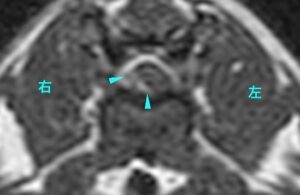

右画像でお腹側から脊髄が圧迫されており(水色矢頭)、そこが造影剤によって白く染まったため、椎間板ヘルニアが今回の麻痺の原因と考えられた。